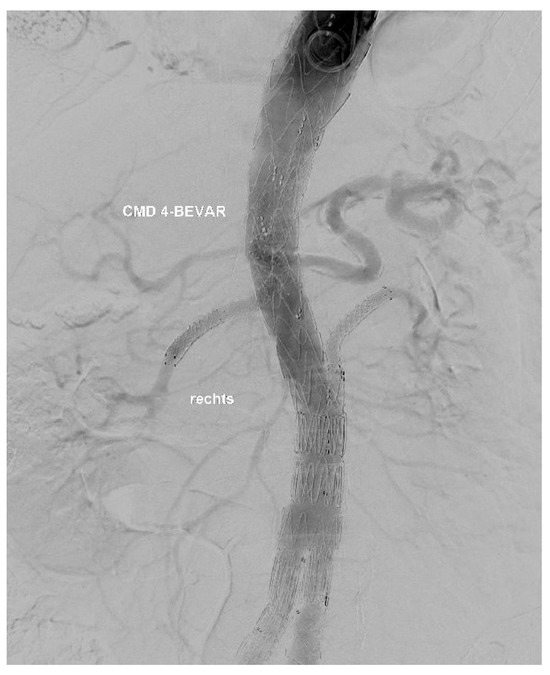

At the end of every operation, an angiography was performed to obtain an overview regarding if the BSGs are patent and if there is any sign of an endoleak of any type (Figure 3 and Figure 4).

Figure 4. Result of a procedure.